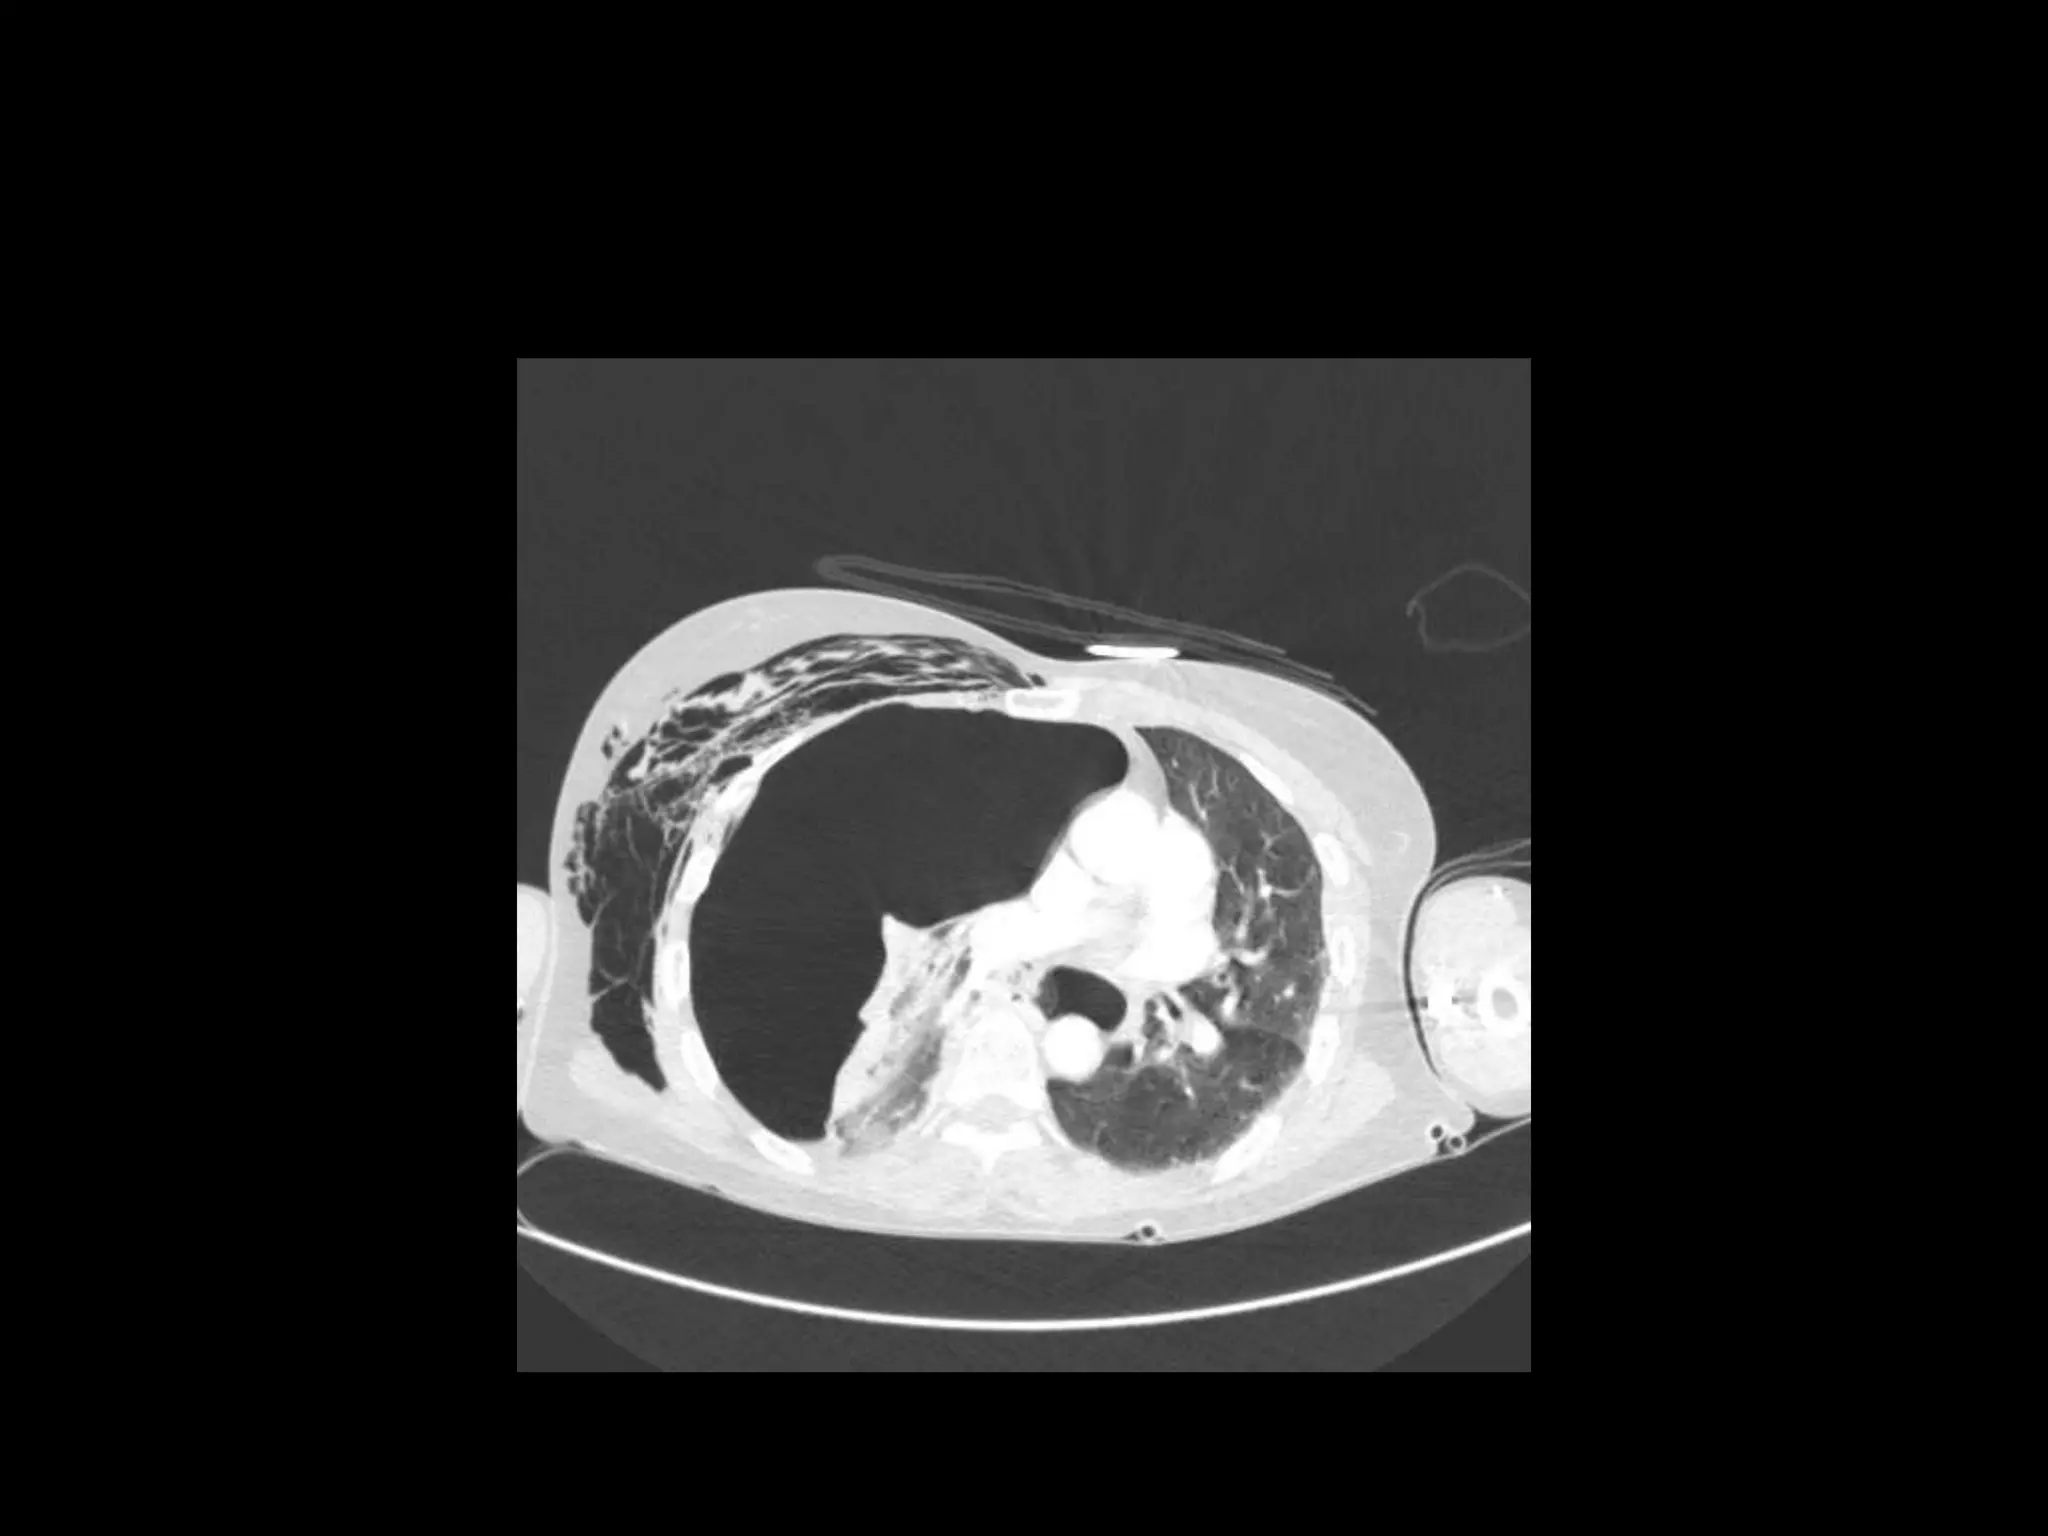

CT Scan - H1N1 Influenza

Ultrasound Findings

• Surgical emphysema

• Small pneumothorax

• Widespread patchy consolidation

• H1N1 pneumonitis